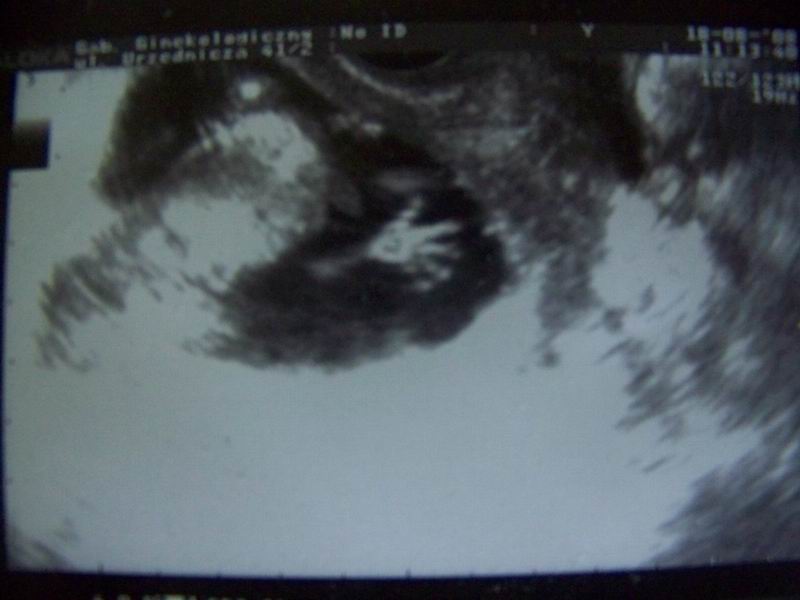

A oto moja dzidzia - 13 tydz i 2 dni:

Widać jak się drapie raczką po główce :-D